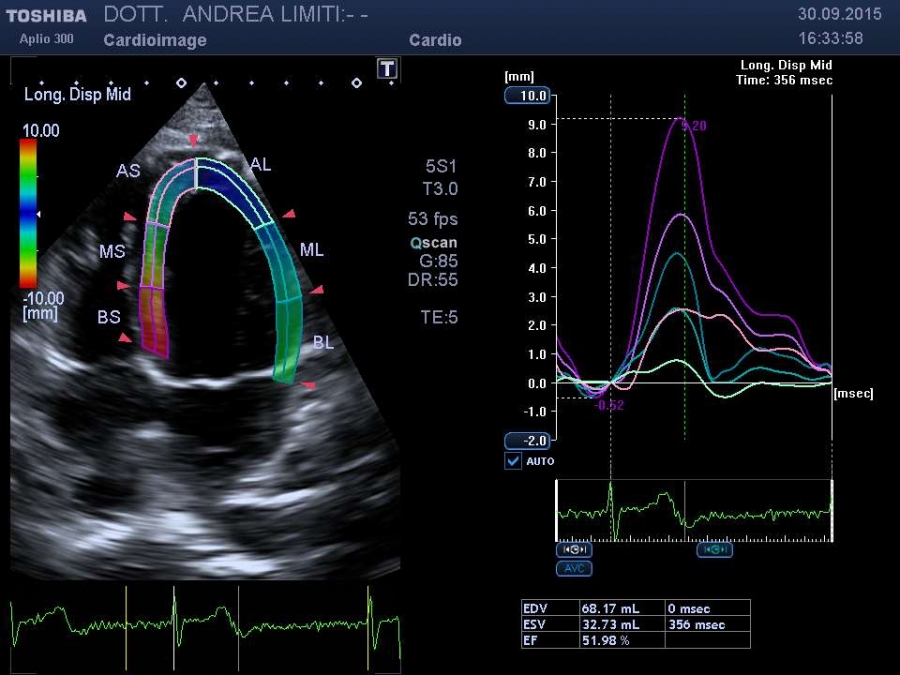

La visita cardiologica, l’Elettrocardiogramma e l’Ecocardiogramma bidimensionale Color Doppler transtoracico consentono di acquisire una ricchezza di informazioni sullo stato anatomico e funzionale del cuore di livello molto elevato che spesso consentono un primo accurato inquadramento dei problemi cardiologici del paziente. E’ importante tuttavia sapere che, anche con gli apparecchi più avanzati, l’ecocardiografia non offre una valutazione diretta dello stato delle coronarie e quindi l’esame non può essere discriminante per la valutazione di sospetti dolori cardiaci.